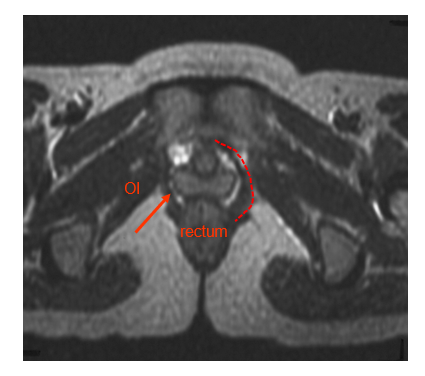

• The red dotted line and arrow indicate the position of the fibres of puborectalis as they pass around the rectum.

The fibres of pubococcygeus pass from the pubic bones to wrap around the prostate gland or vagina and the rectum. Fibres that support the vagina and prostate gland insert into the perineal body and are often given specialist names (levatore prostatae and pubovaginalis) to indicate their function but they are still part of pubococcygeus muscle. In both sexes the more posterior fibres of pubococcygeus wrap around the rectum and are called puborectalis.

• Puborectalis

•Fibres mix with those from external anal sphincter, modified as a sling around the rectum to help maintain faecal continence

The thickened fascia above obturator internus provides an attachment site for the iliococcygeus part of the levator ani muscles that form the pelvic floor. Obturator internus also acts to support the lateral pelvic wall covering the opening of the obturator foramen.

•Attaches to fascia of obturator internus (OI) and the anococcygeal body/ligament/levator plate

•Area of attachment to the fascia of obturator internus described as the tendinous arch of levator ani